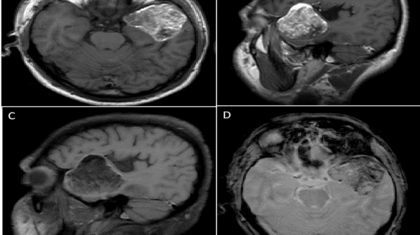

A 30 year old man, presented with complaints of severe headache and vomiting since 4 days.

No history of trauma. No focal neurological deficits.

No significant past history.